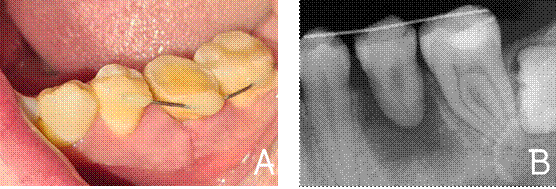

extraoral del diente donador fue menor a 30 segundos. Se ferulizó

con alambre de ortodoncia de grosor 0.02 mm unido con resina en las superficies

vestibulares del diente donador y de los dientes adyacentes por un lapso de 3

semanas (Figura 5A y 5B).

Figura 5.

A) Vista clínica del diente donador en posición interoclusal,

ferulizado con alambre

de ortodoncia y resina. B) Radiografía periapical final.